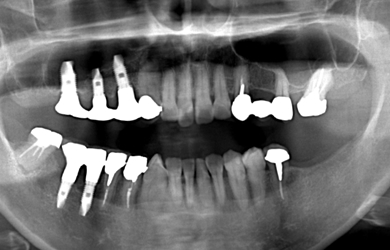

治療後

• 治療後

治療方針 右上の骨がほとんど無いため、サイナスリフト法に再生療法を組み合わせ上顎洞底部を挙上することにより、骨の無い部分に骨をつくってあげ、インプラント治療を可能にする。

治療内容 インプラント5本(抜歯即日スピードインプラント+サイナスリフト+GBR+クラウンレングスニング)、ハイブリッドセラミック8本

治療部位

6 5 4 3

7 6 5 4

総治療費 2,426,400円

治療期間 9.5ヶ月